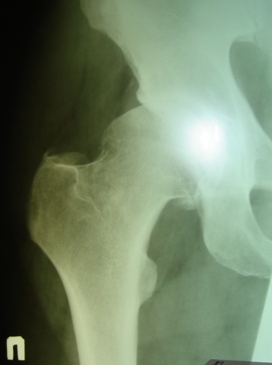

Имя     : Январь 2005-правый.JPG

Тип     : image/jpeg

Размер  : 32857 байтов

Описание: отсутствует

Url     : http://weborto.net:8080/pipermail/ortho/attachments/20090520/789da7ae/attachment-0003.jpeg